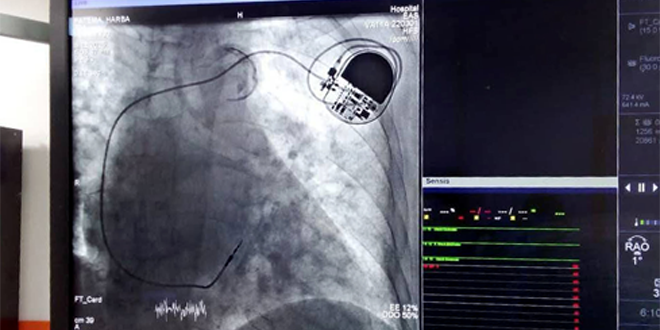

أجريت في مشفى ابن الوليد في محافظة حمص خلال الأيام الماضية، أول عمليتي تركيب جهاز ناظم خطى القلب دائم لمريضتين، الأولى في الـ 68 من العمر والثانية في الـ 80، كانتا تعانيان من حصار قلبي تام منذ سنوات.

وبين مدير مشفى ابن الوليد الدكتور محمد المحمد في تصريح لمراسلة سانا أنه تم تركيب جهاز داعم للقلب (بطارية) للمريضتين، حيث كانتا تعانيان من حصار قلبي، بسبب عدم انتقال الإشارات الكهربائية من الأذين إلى البطينات، مما تسبب ببطء معدل ضربات القلب وشعور بالدوار وفقدان الوعي أحياناً.

وأضاف المحمد: إن عملية ناظم خطى القلب تحسن نوعية حياة المرضى، الذين يعانون من اضطراب نظم القلب، وبالأخص المرضى ذوو الآفات القلبية المسببة لتباطؤ النظم، وهو أمر محدد للنشاط، ويسيء لحياة المريض، وأشار إلى أن إجراء العملية بالمشافي الخاصة مكلف جداً وتصل قيمته لحوالي ثلاثة آلاف دولار، بينما قُدمت الخدمة في مشفى ابن الوليد مجاناً، ويتكلف المريض ثمن الجهاز فقط في المشفى.